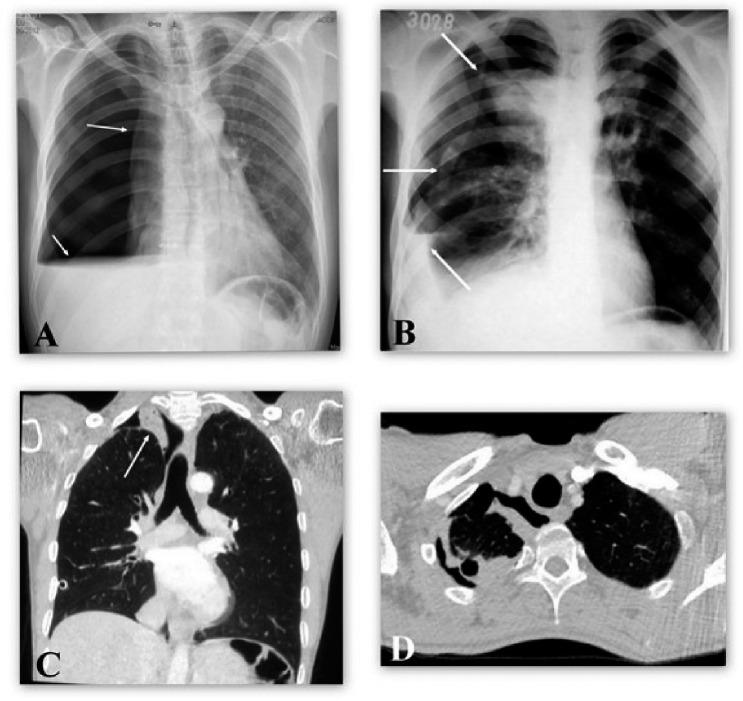

Rev Esp Quimioter. 2021 Feb;34(1):64-66. doi: 10.37201/req/070.2020. Epub 2021 Jan 2.